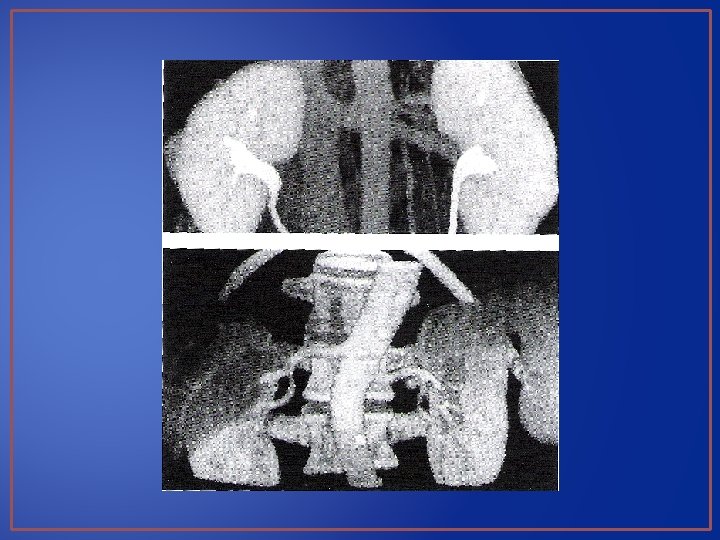

Urografía excretora se observa litio de 11 x 7 mm en el tercio superior del uréter izquierdo Urografía excretora donde se observa un retraso en la eliminación del riñón izquierdo con pielocaliectacia moderada.

Placa simple de abdomen y urografía excretora.